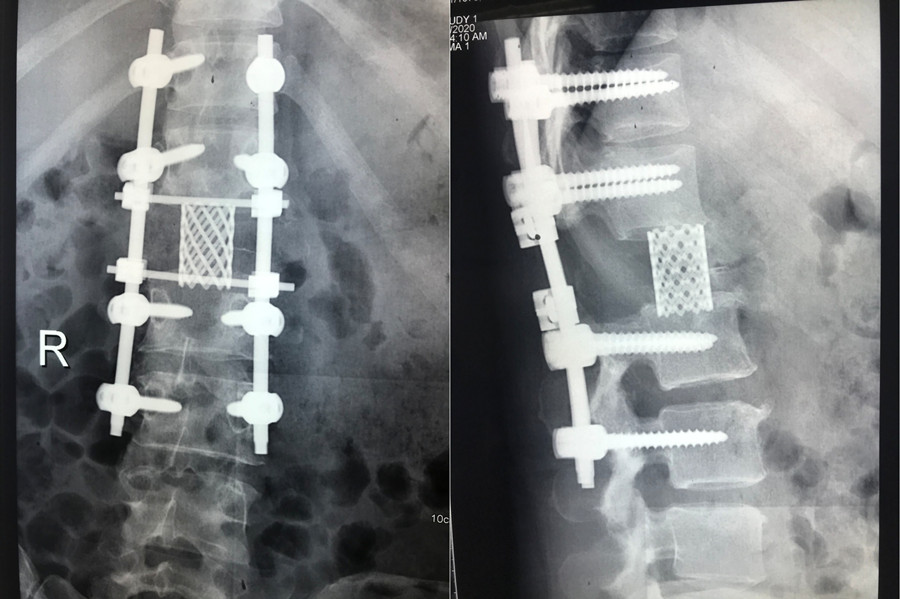

该患者家庭经济拮据,且疫情期间无法外请北京专家前来手术,患者及家属辗转自治区多家医院找到赵岩医生,赵岩团队经过反复讨论和充分准备,最终在麻醉科(手术室)紧密配合下独立完成一期后路固定+En-bloc腰1椎体肿瘤切除术+椎体重建术,该手术首先行后路脊柱固定,其次从后方经椎弓根将病变节段的后部结构整块切除,再向前方分离骨膜和椎体周围血管(这是手术风险最大的步骤),分离彻底后将椎体一并整块切除,最后重建脊柱前中柱。

脊柱截骨手术分六级,此手术属五级截骨手术(VCR),是单椎体最高级截骨手术。术中克服了没有介入科血管栓塞辅助支持等重重困难,最终整个手术仅耗时2个小时顺利将肿瘤椎体完整切除并行腰1椎体重建,出血量500ml。

该手术的成功实施不仅体现了我院脊柱外科对En-bloc技术的熟练掌握,更成功填补了自治区内利用En-bloc技术行脊柱肿瘤手术的技术空白,标志我院脊柱外科技术达到国内一流水平。

术后